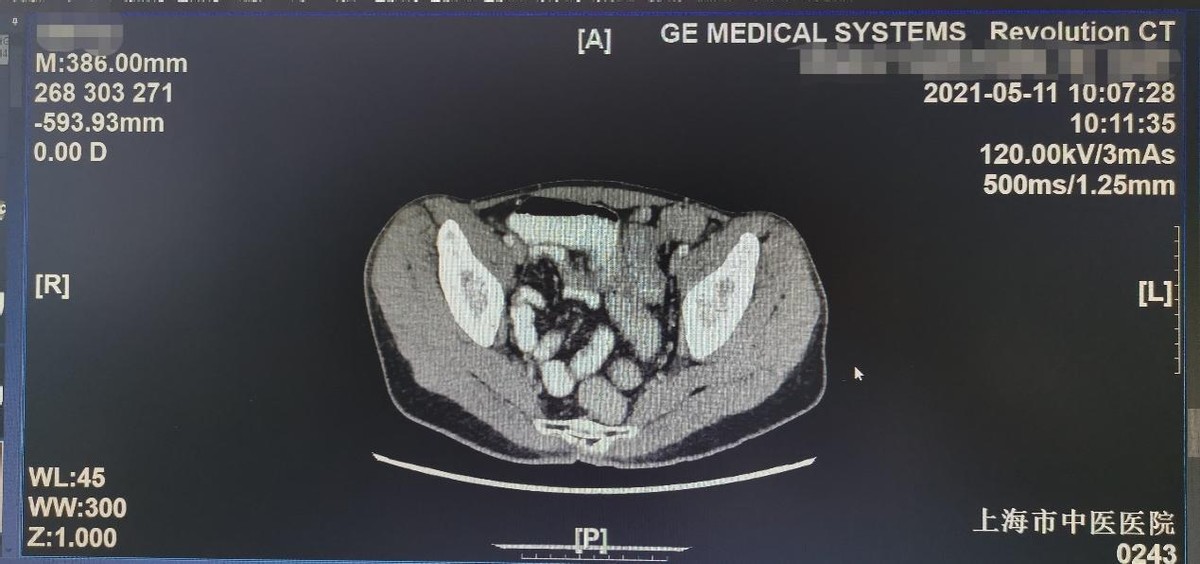

第二天,他带着多年的病历资料来到朱光辉主任的门诊,朱主任仔细研究分析了他的病情,并帮他检查了腹部CT,发现不单单是乙状结肠狭窄的问题,还合并有多发的小肠结肠内瘘,如果不及时治疗,患者随时有可能出现肠瘘、腹膜炎等病情危重的情况,必须赶紧住院治疗。经过朱主任详尽的解释,小王决定住院接受外科手术治疗,术前完善的准备工作也让小王放心许多。手术当中朱主任发现小王的小肠和结肠粘连在一起,扭曲成团,形成了数个小肠结肠内瘘,术中朱主任再次和家属谈话沟通后,将有炎症和内瘘病变的小肠全部切除,保留了剩余的小肠,同时将病变的乙状结肠也完整切除。术后,在外一科医护人员精心的治疗下,小王恢复很快,已经顺利出院。 上海市中医医院 外一科(胃肠外科),为复旦大学附属中山医院普外科技术合作点,朱光辉主任专家门诊时间:周一上午、周四上午。